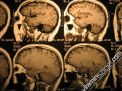

» Cikkek \ + Prevenció - megelőzés \ + Vizsgálatok, szűrések \ + MRI (Magnetic Resonance Imaging) |

MRI (Magnetic Resonance Imaging)